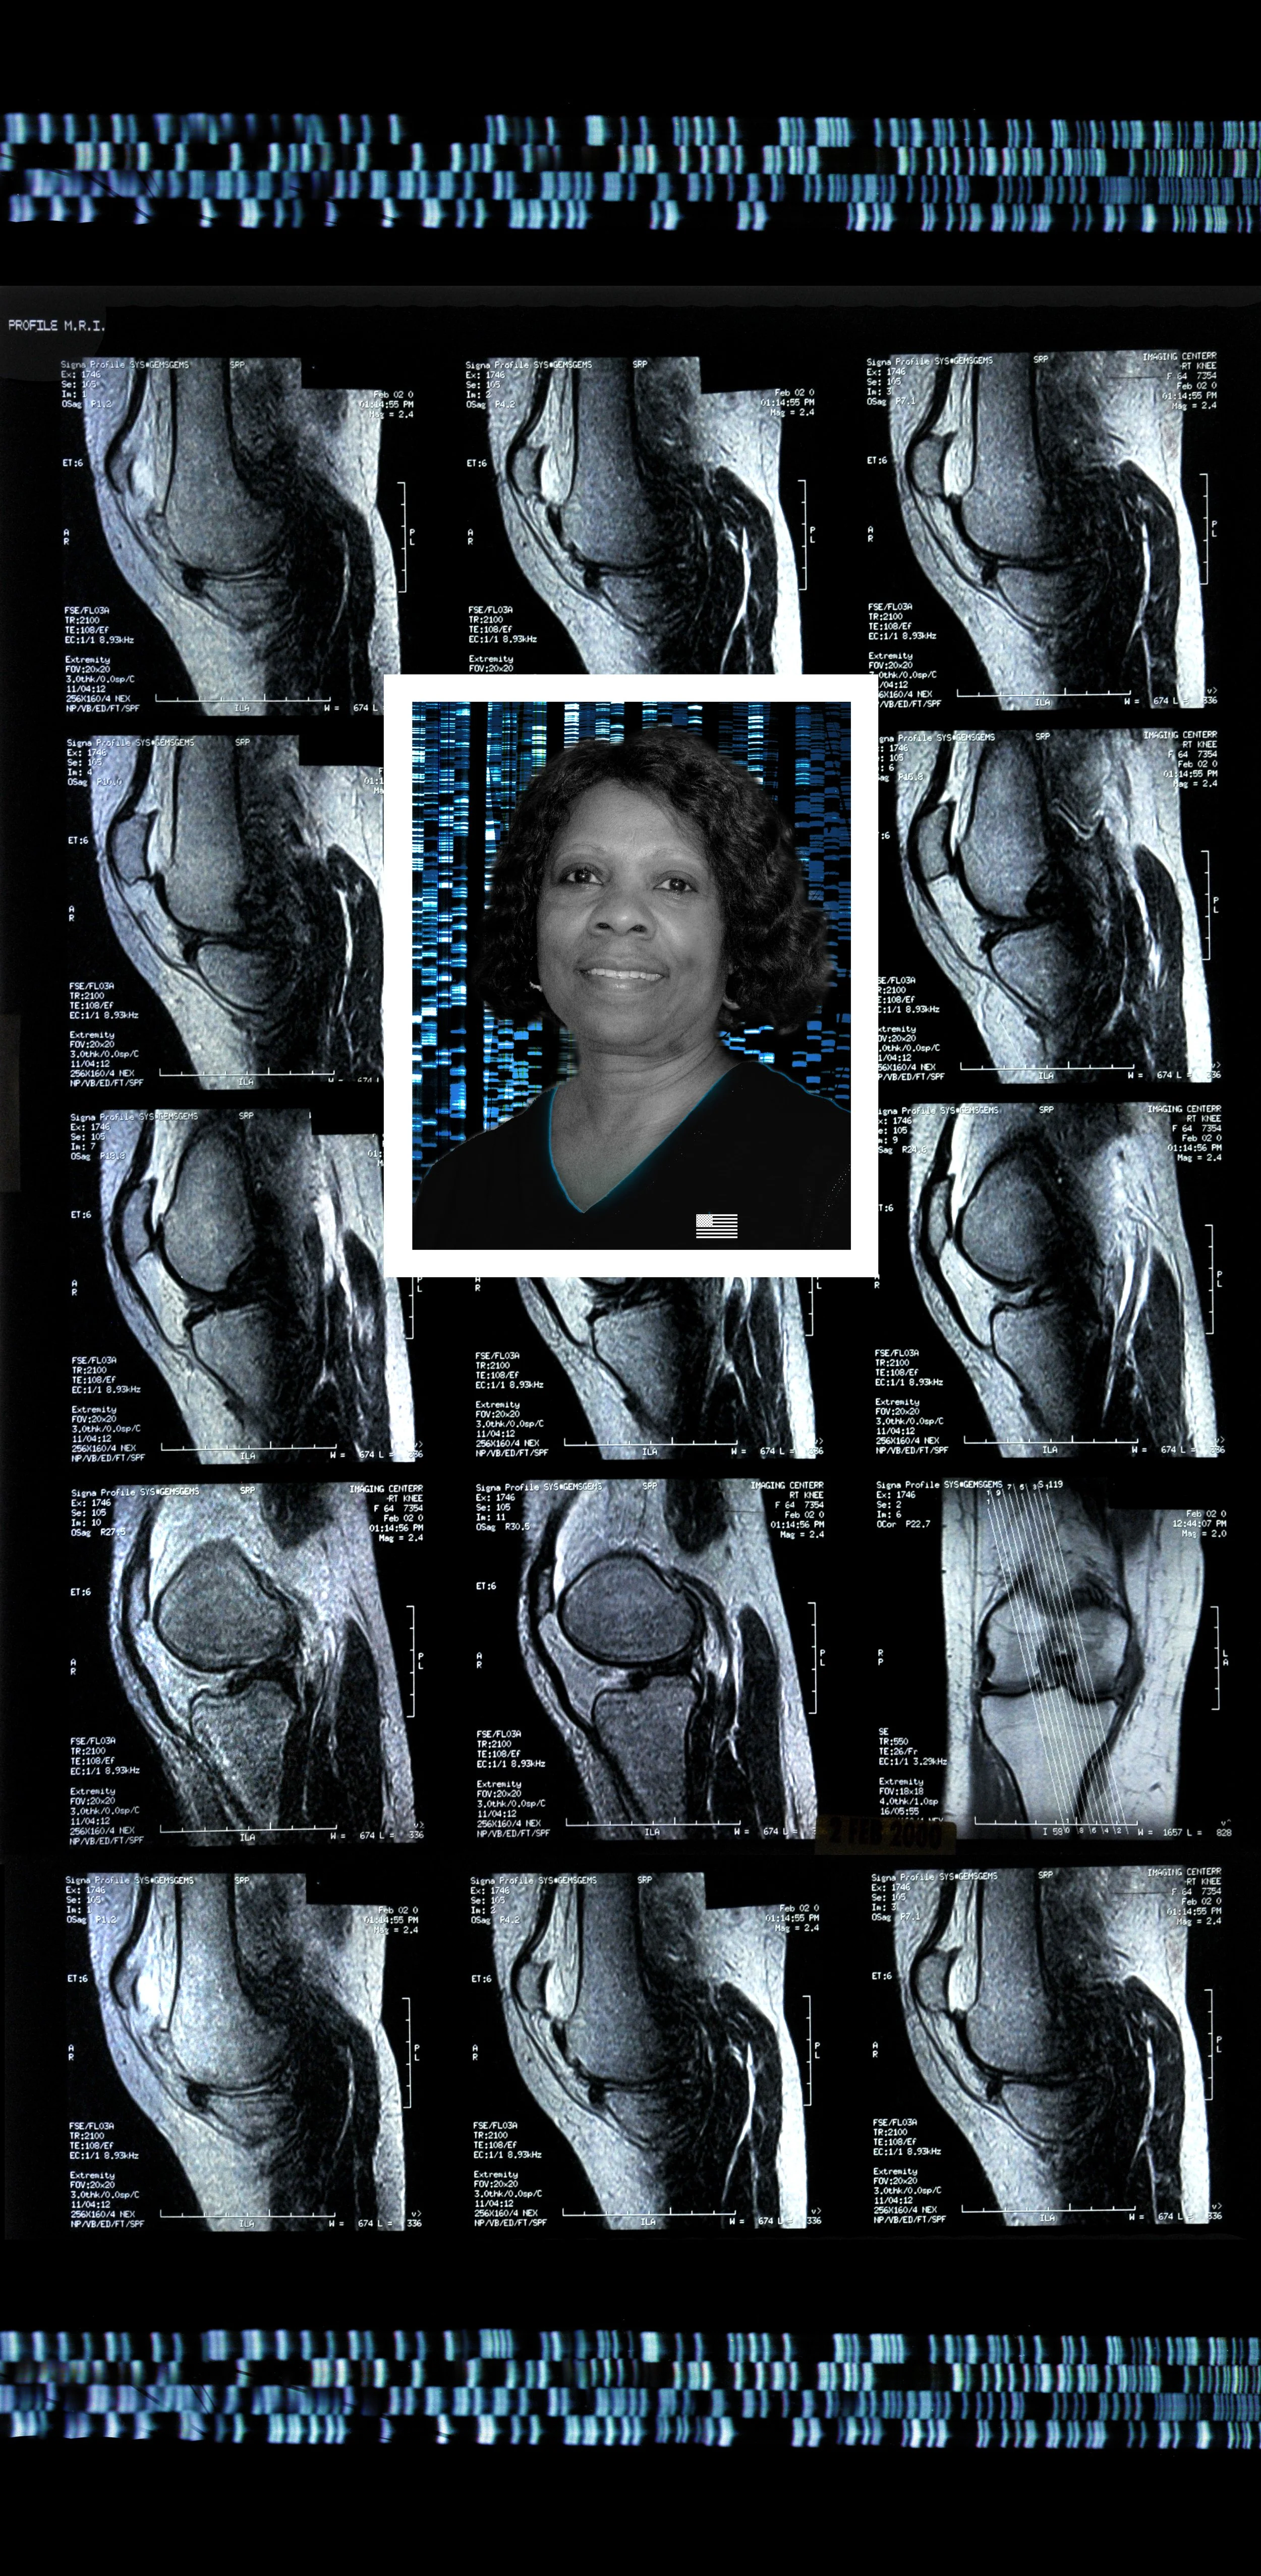

Comprising eight 47” x 23” backlit Plexiglas panels, each work features a portrait, often of individuals from diverse racial, ethnic, and cultural backgrounds. Surrounding these portraits are embedded CT scans, MRIs, and DNA sequencing gels. These medical images, reimagined as expressive symbols, evoke biological inheritance, invisible histories, and interior experience rather than clinical diagnosis.

Used metaphorically, DNA strands suggest ancestral continuity; CT scans and MRIs hint at the unknowable workings of body and psyche; ghostly anatomical forms recall trauma, resilience, and emotional scars. By pairing portraiture with interior imaging, the series questions how we perceive identity. Are we defined by surface appearance—skin, gender, dress—or by memory, genetics, and lived medical experience? Can scientific data be truly neutral, or does it reflect cultural bias and interpretation?

Black Lady 47” x 23”